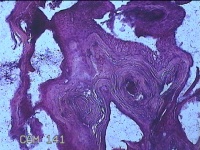

性别

男

年龄

33岁

临床诊断

寻常疣

一般病史

面部起丘疹2年余。

标本名称

面部丘疹

大体所见

灰白暗红色不规则组织0.7x0.5x0.3cm一堆。